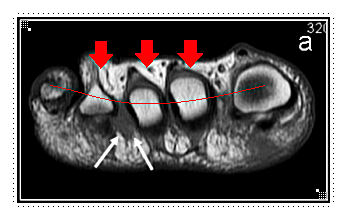

지간신경종은 말 그대로 발가락 사이의 신경이 눌리거나 자극을 받아 염증이 생기는 질환입니다.

하지만 실제로는 종양이 아니라, 지속적인 압박으로 신경이 두꺼워지는 현상에 가깝습니다.

발바닥 구조를 보면 신경이 발가락 뼈 사이를 지나갑니다.

굽이 높은 신발이나 앞이 좁은 신발을 자주 신으면 신경이 눌려 통증, 저림, 화끈거림 등의 증상이 생기죠.